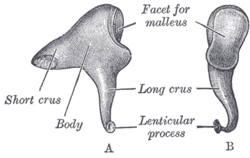

Left incus. A. From within. B. From the front. | |

The incus is the second of the ossicles, three bones in the middle ear which act to transmit sound. It is shaped like an anvil, and has a long limb and a short limb that protrude from the point of articulation with the malleus.[2]:862